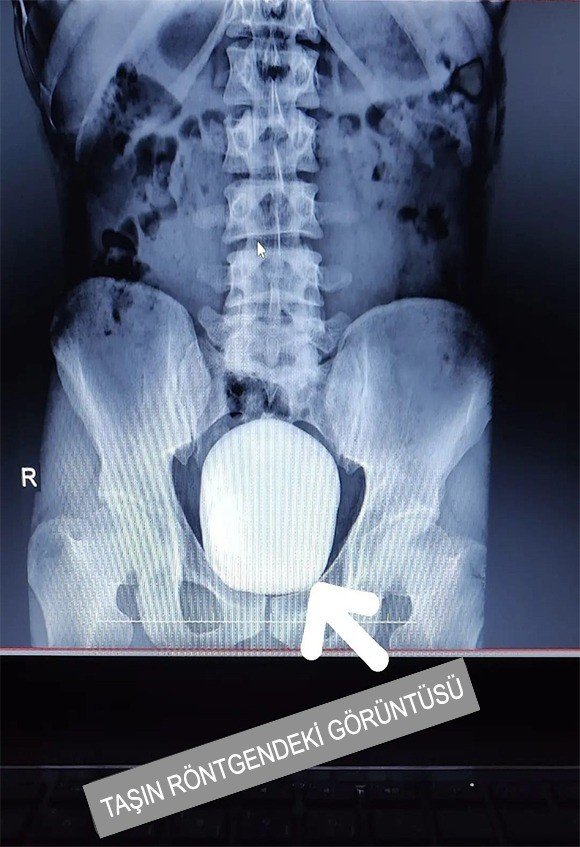

Karaman’da Bir Hastanın Mesanesinden 15x10 Ve 4x3 Büyüklüğünde 2 Taş Çıktı

Karaman'da idrar yanma şikayeti ile hastaneye baş vuran bir hastanın mesanesinden 15x10 ve 4x3 santim büyüklüğünde 2 adet taş çıkarıldı.

Edinilen bilgiye göre, 27 yaşındaki B.Y., isimli hasta idrar yanması şikayeti ile Karaman Eğitim ve Araştırma Hastanesine başvurdu. Çekilen röntgeninde hastanın mesanesinde 2 adet büyük çapta taş tespit edildi. Doç. Dr. Güven Erbay ve Dr. Öğretim Üyesi Ahmet Şanlı tarafından yapılan cerrahi operasyonla hastanın mesanesindeki 2 taş başarılı bir şekilde alındı.

Başarılı geçen ameliyatla ilgili konuşan Doç. Dr. Güven Erbay, "Hastamız idrar yanması şikayeti ile kliniğimize başvurdu. Yaptığımız tetkikler ve görüntülemeler sonucunda mesane içinde 15x10 santim dev boyutta bir adet ve mesane içindeki divertikül içinde de yaklaşık 4x3 santim olmak üzere toplamda iki adet taş tespit ettik. Literatürde tüm dünya genelinde kayıtlara geçen en büyük mesane taşının ağırlığı bin 900 gram olduğu bilinmektedir. Çıkarılan taşların toplam ağırlığı bin 50 gram olarak tespit edildi. Bu büyüklükteki ve ağırlıktaki dev mesane taşının Türkiye sınırları içerisinde çıkarılan en büyük mesane taşı olduğunu düşünmekteyiz" dedi.